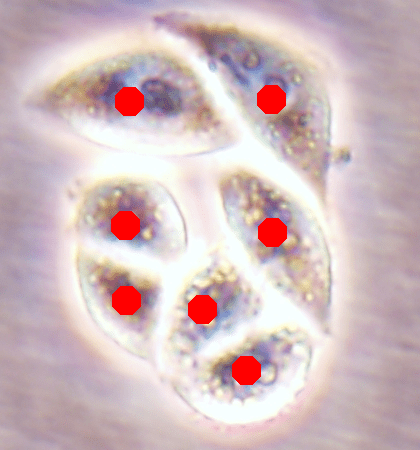

Since the main goal of this work is cell detection, our DeepDistance models define the estimation of an inner distance map as the main task and find regional maxima on this estimated map to detect cells. The motivation behind these choices is the fact that the inner distance definition gives sharp increases at cell centers and the locations with these sharp increases can be detected by finding regional maxima. Hence, to obtain accurate detections, one should estimate an inner distance map with distinct differences between the cell centers and their surrounding pixels such that these centers can be identified as regional maxima. That is, one should estimate a map consisting of sharp enough bright regions close to the cell centers. To improve the performance of the task of this inner distance estimation, our models take advantage of multi-task learning approach. This approach helps the models become more robust to avoid overfitting a task, compared to the approach of learning the same task alone with a single-task model (Caruana, 1997). To get more insight in this multi-task learning approach, this section visually analyzes the estimated maps of single-task and multi-task models.

![]() |

| (a) | (b) | (c) | (d) |

For the independent test samples given in Fig. 4, Fig. 6a shows the maps of the calculated inner distances when the ground truths are given. Figs. 6b, 6c, and 6d illustrate the inner distance maps estimated by the SingleInner method, the proposed DeepDistance model, and its extended version, respectively. SingleInner learns its map as a single-task whereas our models define auxiliary tasks and learn the inner distance map in parallel to these auxiliary tasks, forcing them to learn shared representations with a shared encoder path. The latter type of learning, which is an example of multi-task learning, is known to be effective for increasing the performance of individual tasks for many domains. We also observe this performance increase in the estimated maps given in Fig. 6. SingleInner cannot successfully detect the three cells shown inside red ellipses since it cannot produce sharp enough bright regions (with distinct enough estimated distances) for these cells. Although DeepDistance, which uses one auxiliary task, leads to brighter regions for these cells, they are still not sharp enough for two of them to be identified as regional maxima. The extended version of DeepDistance, which uses one more auxiliary task, does better job in inner distance estimations such that they have sharp enough bright regions for all of these three cells.

In this figure, it is worth to noting two points: First, all methods apply the h-maxima transform on their estimated maps beforehand to suppress noise, and hence, to prevent over-segmentations and false positives. If it was not applied, SingleInner might give regional maxima for some of the three cells even though the distances estimated for their centers were not that distinct (bright). However, that case would also give many over-segmented cells and false positives. Second, none of the methods identify the cell shown inside a blue ellipse although their estimated distances yield bright regions for this cell. It is due to the evaluation method, which matches an annotated marker and a detected cell based on the distance between them since a test set image does not have boundary annotations but just a dot on each cell. In our experiments, a distance threshold is set to 30, considering image resolutions and the average cell size. This threshold may give a few incorrect matchings especially for larger cells, (e.g., the cell shown inside the blue ellipse). Increasing this threshold solves the problem for this particular cell, but this time, it will result in many incorrect matchings of detected cells with distant markers (or vice versa).